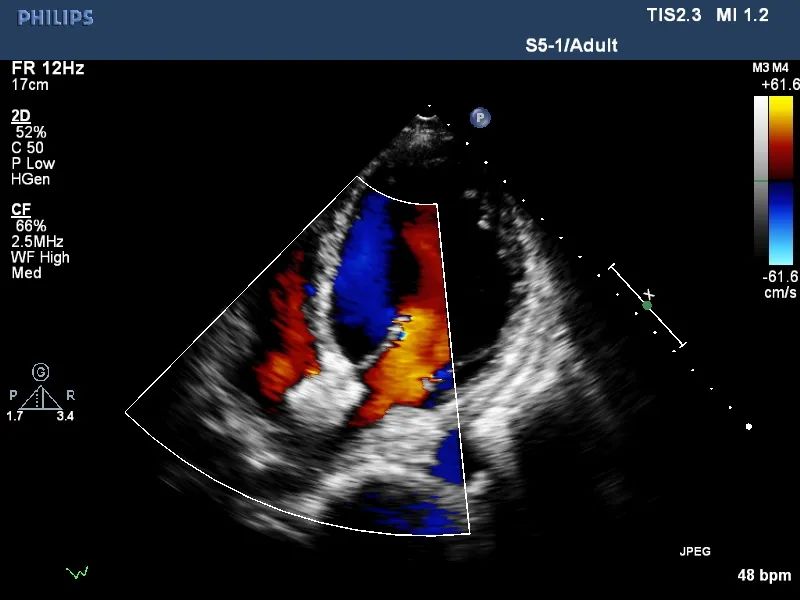

此次来空军军医大学西京医院治疗的患者是名56岁男性,间歇性气短胸闷3年余,长期药物治疗无明显改善,至西京医院就诊。入院后超声提示二尖瓣返流,长度6.6cm,面积9.4cm²,容积11ml。EDV:215ml,ESV:133ml,EF:30%,FS:16%,SV:82ml。初步诊断:心脏瓣膜病,二尖瓣关闭不全,心功能衰竭。经心脏团队讨论,决定采用D-shant为患者行局麻心房分流器置入术。

术前超声